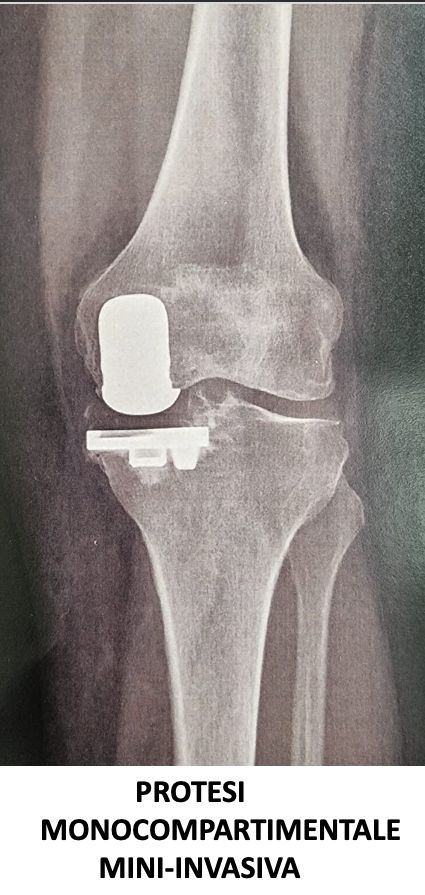

Nel 2018 frequenta come “Academic Observator” l’U.O. di Ortopedia “CDC Sileno e Anna Rizzola” di San Donà di Piave dedicandosi alla protesica di ginocchio con protocollo “fast-track”, pubblicando articolo su rivista internazionale intitolato “Experience-optimised fast track improves outcomes and decreases complications in total knee arthroplasty”.

Svolge la sua attività presso l’Ospedale del Mare, occupandosi di chirurgia traumatologica, con predilezione alla protesica di ginocchio e medicina rigenerativa della cartilagine articolare.